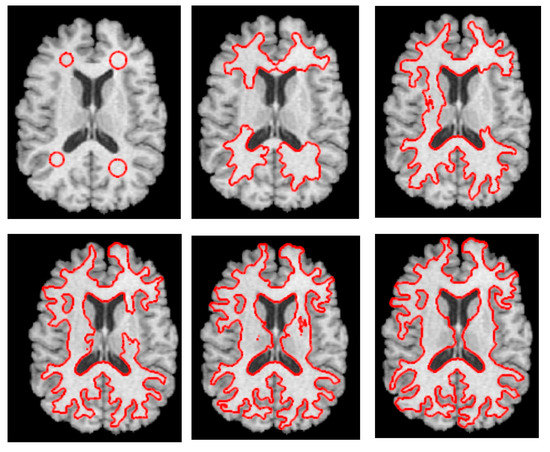

3.1. Step 1 Preprocessing Phase

3.2. Step 2 Quantum Dragonfly-Based Clustering Phase

3.2.1. Initial DA’ Food Sources Extraction Using K-Mean Algorithm

3.2.2. Determine Initial Contour Points Using Quantum Dragonfly Algorithm

3.3. Step 3 Level Set Segmentation